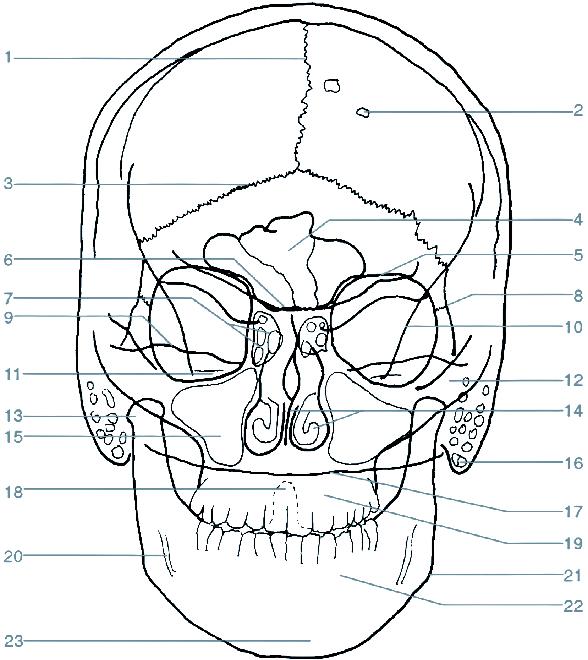

1 sutura sagittalis (šev šípový)

2 foveolae granulares

3 sutura lambdoidea (šev lambdový)

4 sinus frontalis (dutina kosti čelní)

5 strop orbity (očnice)

6 planum sphenoidale

7 cellulae ethmoidales (etmoidální sklípky / dutinky kosti čichové)

8 sutura frontozygomatica (šev mezi kostí čelní a kostí lícní)

9 horní hrana pyramidy (kosti skalní)

10 linea innominata

11 meatus acusticus internus (vnitřní zvukovod)

12 arcus zygomaticus (jařmový oblouk)

13 caput mandibulae (hlavice dolní čelisti)

14 septum nasi et concha nasalis inferior (nosní přepážka a dolní nosní skořepa)

15 sinus maxillaris (dutina horní čelisti)

16 processus mastoideus (bradavkový výběžek)

17 squama occipitalis (šupina kosti týlní)

18 dens axis (zub čepovce)

19 maxilla (horní čelist)

20 canalis mandibulae (kanál v dolní čelisti)

21 angulus mandibulae (úhel dolní čelisti)

22 mandibula (dolní čelist)

23 protuberantia mentalis (bradový výběžek)

os frontale (kost čelní)

os occipitale (kost týlní)

os temporale (kost spánková)

os zygomaticum (kost lícní)

os parietale (kost temenní)

os sphenoidale (kost klínová)